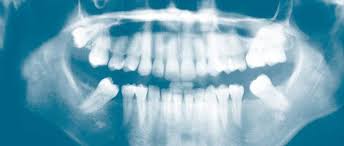

Die gesamte Mundsituation Frage vom. 2x ist sicher besser aber die Entscheidung wie oft man das macht lasse ich mir nicht vom Zahnarzt. Die daraus resultierende Strahlendosis liegt bei 2 mSv Milli-Sievert.

Bei mir müßten die gesamten Zähne mehrmals sehr oft in diesem Jahr geröntgt werden. Wie oft sollte man sich im Jahr nur höchstens beim Zahnarzt röntgen lassen. Bereits 2009 wurden 2 Aufnahmen gemacht.

Menschen die einmal oder mehrmals jährlich beim Zahnarzt geröntgt. Wie oft darf man sich pro Jahr röntgen lassen.